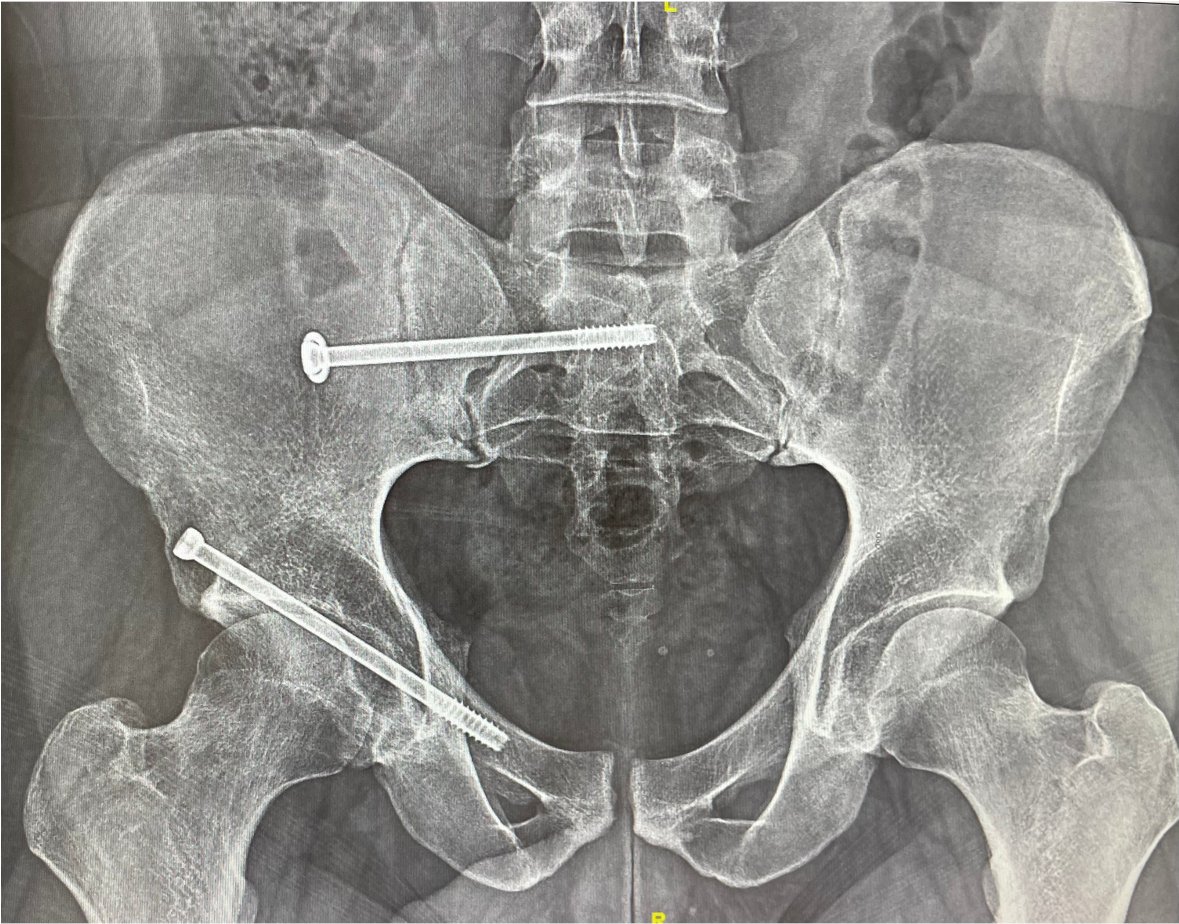

Percutaneous acetabular fixation

Dr. Diego López tweet mediaDr. Diego López tweet mediaDr. Diego López tweet media

@suhirad Yes of course! But with good bone, non conminution neither displacement and component tranverse AC fx with SIj fixed, i feel good not to open ischium or lateral window